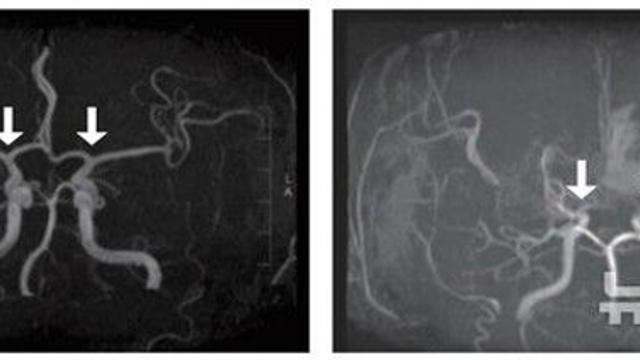

"피 검사로 확진"…소아 모야모야병 조기진단 길 열렸다

사진 = 뉴시스   간단한 혈액 검사만으로도 소아 모야모야병을 조기 진단할 수 있는 길이